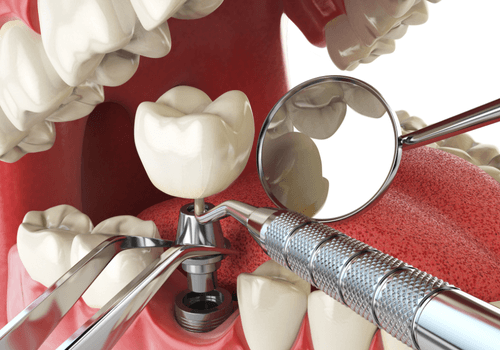

Crown and Bridge

Custom ceramic restorations to rebuild broken teeth or replace missing ones seamlessly.